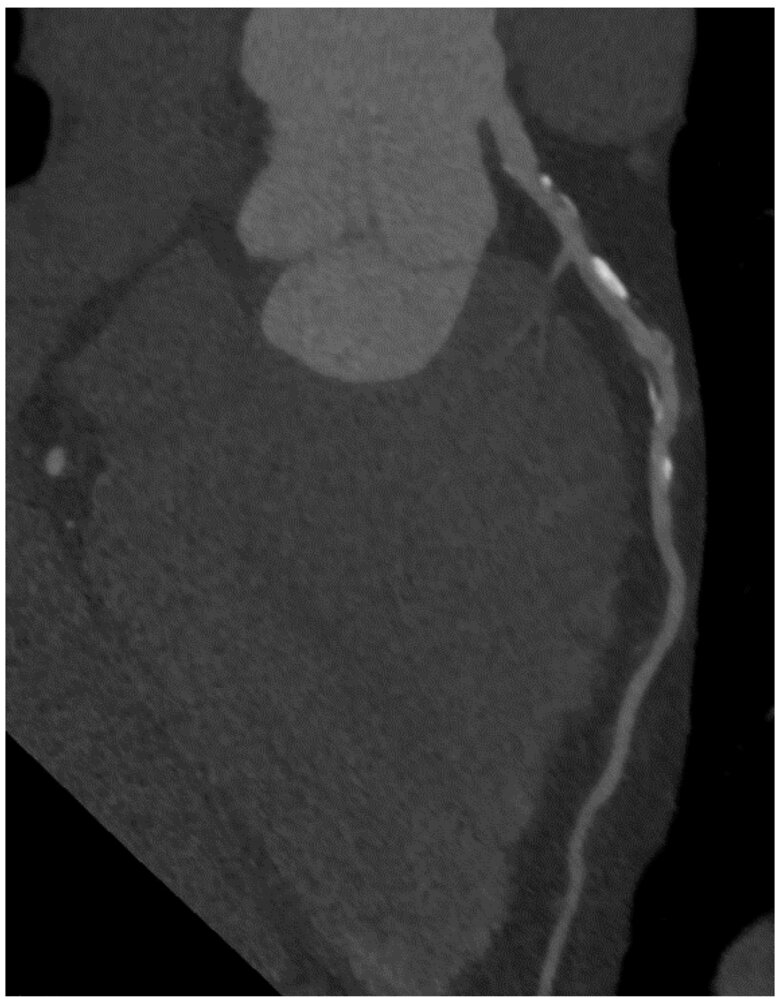

Coronary CT angiography (CCTA) [10][11][12]

• Description: a noninvasive contrast-enhanced radiological study used to visualize the coronary arteries on cardiac CT [13]

• Common uses

• Evaluation for CAD in selected patients, e.g., with stable angina and intermediate to high PTP for obstructive CAD [14]

• Assessment after revascularization

• Evaluation of cardiac structure and function, e.g., in adult congenital heart disease, heart failure, or valvular disease

Coronary CT angiography is a noninvasive method that can be used to detect obstructive CAD in patients at low to intermediate risk and those with contraindications for stress testing.